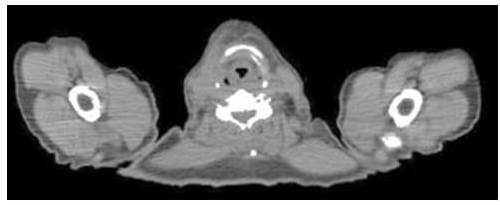

En julio de 2019 el paciente se realiza en PET-IQ-TC que muestra control local completo sin evidencia metabólica de recidiva local, con signos de captación difusa origen pos inflamatorio del tratamiento radiante recibido (Figura 4).